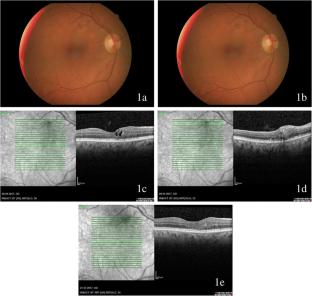

Fig. 1